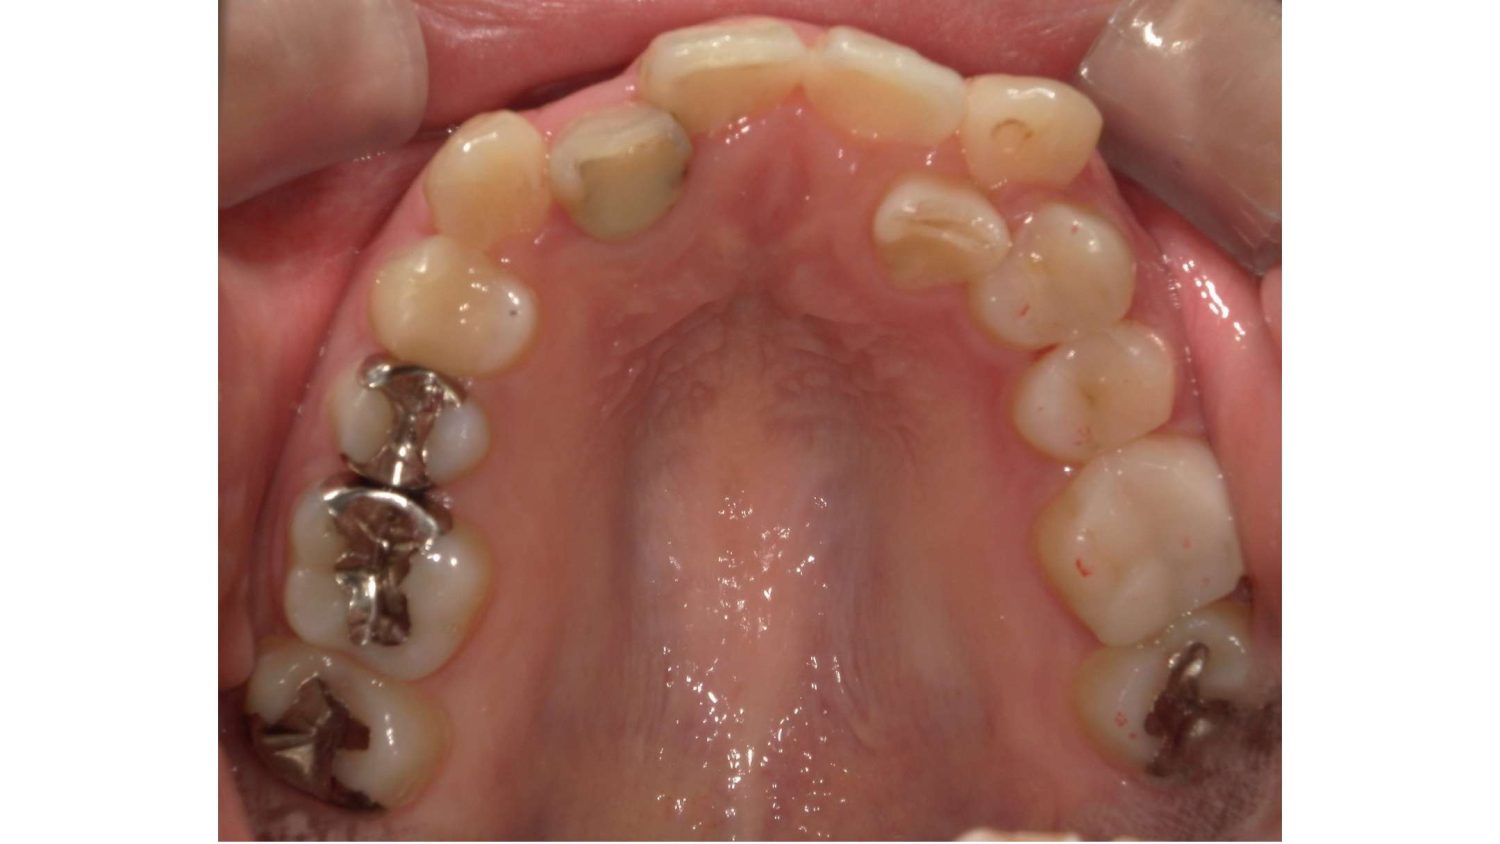

前歯だけの矯正の症例紹介②

Before

主訴

上の前歯の横の歯が後ろに引っ込んでいるのでセラミックの被せ物で治したい。

治療内容

ワイヤー矯正で治しました。

治療費

115,500円(税込)(リテーナー込み)

治療期間

4か月

通院回数

5回

想定されたリスク

※当該部位の上下のかみ合わせが反対になっていましたので、上の歯を前に動かすときに引っかかって動かない可能性がありました。

セラミックの被せ物で治すと健全な歯を削ることになってしまうので、患者様と相談し、矯正治療で治すことにしました。